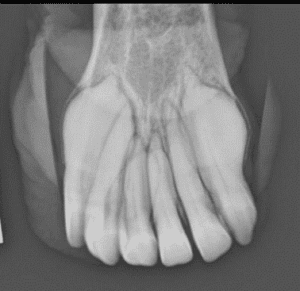

Bei der jĂ€hrlichen Zahnkontrolle von dieser 24-jĂ€hrige Stute fiel bei der Untersuchung dieses Jahr eine VerĂ€nderung der SchneidezĂ€hne auf. Das Zahnfleisch ist aufgetrieben, es befindet sich ĂŒbermĂ€ssigem Zahnstein auf die ZĂ€hnen und auf der rechte Oberkiefer (links im Bild, umkreist) sieht man eine knollige Auftreibung vom Ă€usseren SchneidezĂ€hne. Einzelne ZĂ€hne im Oberkiefer waren zudem etwas locker. Um zu sehen, wie weit die Erkrankung bereits fortgeschritten ist, wurden Röntgenbilder von den SchneidezĂ€hnen im Ober- sowie Unterkiefer gemacht. Dort sah man, dass die ZĂ€hnen auch unter dem Zahnfleisch verĂ€ndert sind, und diese knollige Verformung sich nicht nur auf den einen Zahn begrenzt.

Es steht fĂŒr Equine Odontoclastic Tooth Resorption and Hypercementosis. Das bedeutet, der Zahn löst sich auf (Resorption) und gleichzeitig bildet sich Zement im ĂŒbermĂ€ssigem Mass (Hyperzementose). Das Resultat ist diese knollig-aussehende ZĂ€hne die man bei dieser Stute gefunden hatte. Die klinische Zeichen einer EORTH sind aufgetriebenes Zahnfleisch, Zahnstein im Bereich der SchneidezĂ€hnen, entzĂŒndetes Zahnfleisch, mit oder ohne kleine roten BlĂ€schen (Parodontose) und eine Lockerung der SchneidezĂ€hnen. EOTRH tretet meist bei Ă€lteren Pferden, ab 15 Jahren, auf und ist eine sehr schmerzhafte Erkrankung.